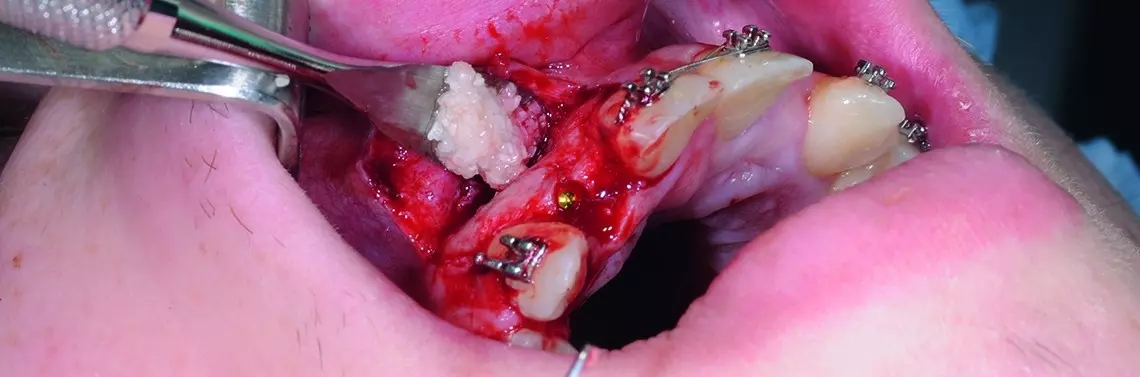

W dniu zabiegu ząb skruszono tak, aby uzyskać drobiny wielkości 800–1000 µm, które są optymalne dla procesu regeneracji kości. Po rozdrobnieniu otrzymano 1,5 cm³ materiału kostnego.

Autogenny materiał kostny pochodzenia zębowego umieszczono w ubytku tak, aby pokrył odsłoniętą powierzchnię implantu. Materiał po nasączeniu krwią był dostatecznie zwięzły i nie wymagał zastosowania dodatkowych membran. Po uwolnieniu okostnej pole operacyjne zostało zamknięte bez napięcia, umożliwiając gojenie podśluzówkowe implantu. Wargowy zarys wyrostka był bardziej wypukły niż przed augmentacją. Zaplanowano odsłonięcie implantów za 3 miesiące.